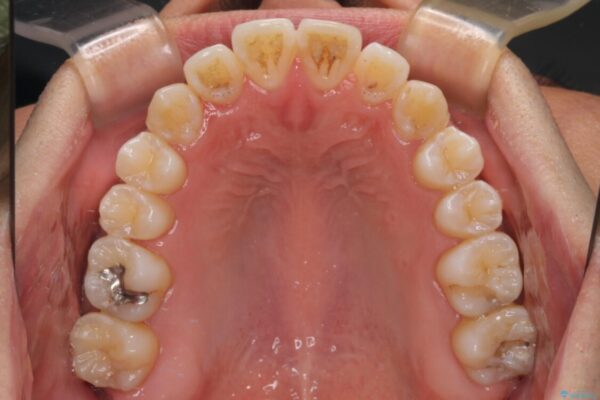

治療前

• 左右の八重歯が気になる ワイヤー装置での咬み合わせ改善 治療前画像